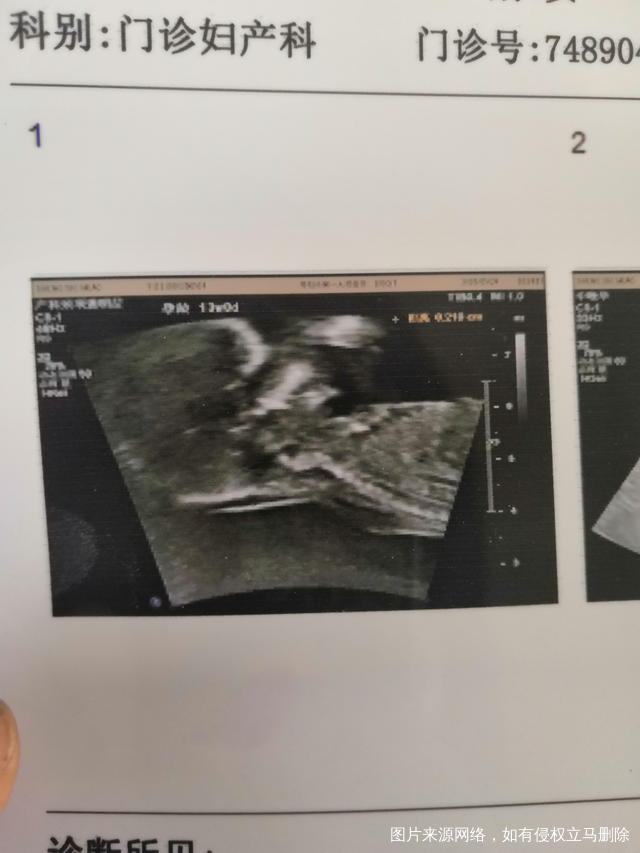

有没有经验帮忙看看性别,

第一个是儿子,这胎想要女儿[冒心心]忘有经验的分享下经验,给点勇气,谢谢😜